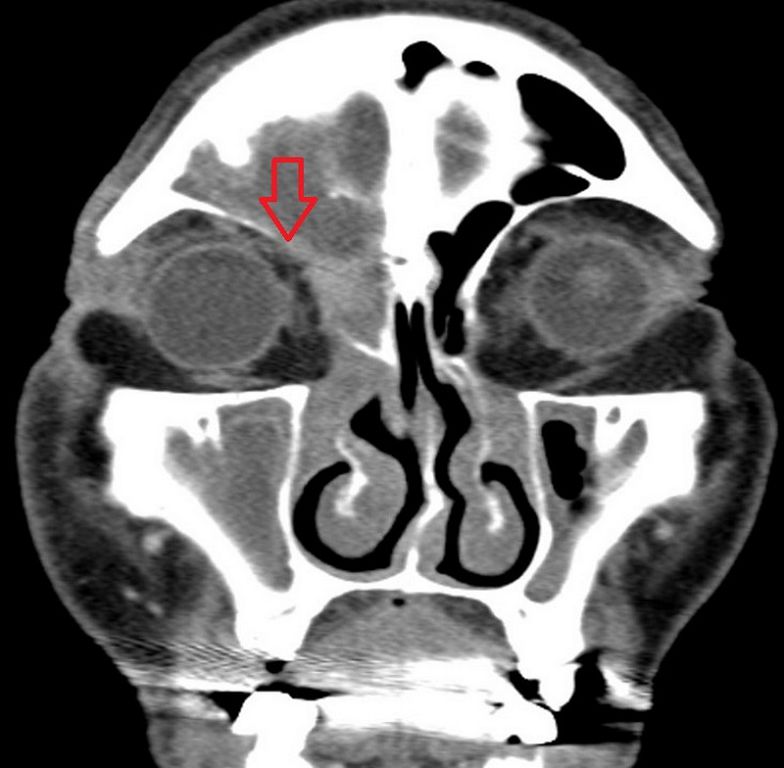

84歲的李爺爺半個月前突然出現右眼腫脹情形,但卻一直不以為意,直到過了兩週出現疼痛、影響視野,才至坊間診所就診,後因症狀嚴重遂轉至台北慈濟醫院急診。在排除眼科疾病後,耳鼻喉科吳姳萱醫師透過電腦斷層發現其鼻竇黏膜腫脹,導致鼻竇開口阻塞,進而影響眼周,出現膿瘍情形,診斷為急性鼻竇炎併發右眼上皮膿瘍,遂執行3D立體定位導航微創鼻竇內視鏡手術及右側上眼皮膿瘍切開引流手術,術後李爺爺症狀緩解,定期回診追蹤。

鼻腔由許多軟骨及硬骨組成,形成大大小小的隔間,分別有額竇、篩竇、蝶竇及上頷竇,主要功能包括減輕頭骨重量、幫助呼吸道保濕與過濾、聲音共鳴及保護腦部與臉部的重要結構,一旦發炎或阻塞,就會導致鼻竇炎。吳姳萱醫師說明:「鼻竇炎依照病程可分為急性(通常小於4週)與慢性(超過12週),病人通常會出現鼻塞、分泌物增加、臉部疼痛、嗅覺減退或喪失等症狀。幼童、長者或免疫力低下的族群就可能因簡單的鼻竇炎而影響周圍器官與組織,從而產生併發症,例如眼眶蜂窩性組織炎及眼膿瘍、腦膜炎、海綿竇栓塞等等。」

鼻竇炎的診斷通常以病史詢問、鼻鏡理學檢查進行,以藥物治療為主要選擇,但若是像李爺爺一樣影響到周圍器官組織,就需透過手術解除病灶。過去鼻竇炎手術是翻開兩邊上嘴唇,在牙齒上方橫切一刀,再將前臉頰的骨頭打開進行手術,術中出血可能影響視野,容易破壞周圍正常組織,導致傷口較大、恢復較慢。而隨著醫療技術的推展,醫師首先可利用3D導航確認病灶,再藉由內視鏡以微創削切刀切除組織。與此同時再透過引流方式,將膿瘍清除。吳姳萱醫師指出:「微創削切刀是一種結合旋轉切割與吸引抽吸功能的器械,透過快速旋轉的刀頭將組織細碎切除,同時將碎屑與分泌物清除,保持視野清晰,如此便能減少對正常組織的破壞,手術傷口也相對較小。」